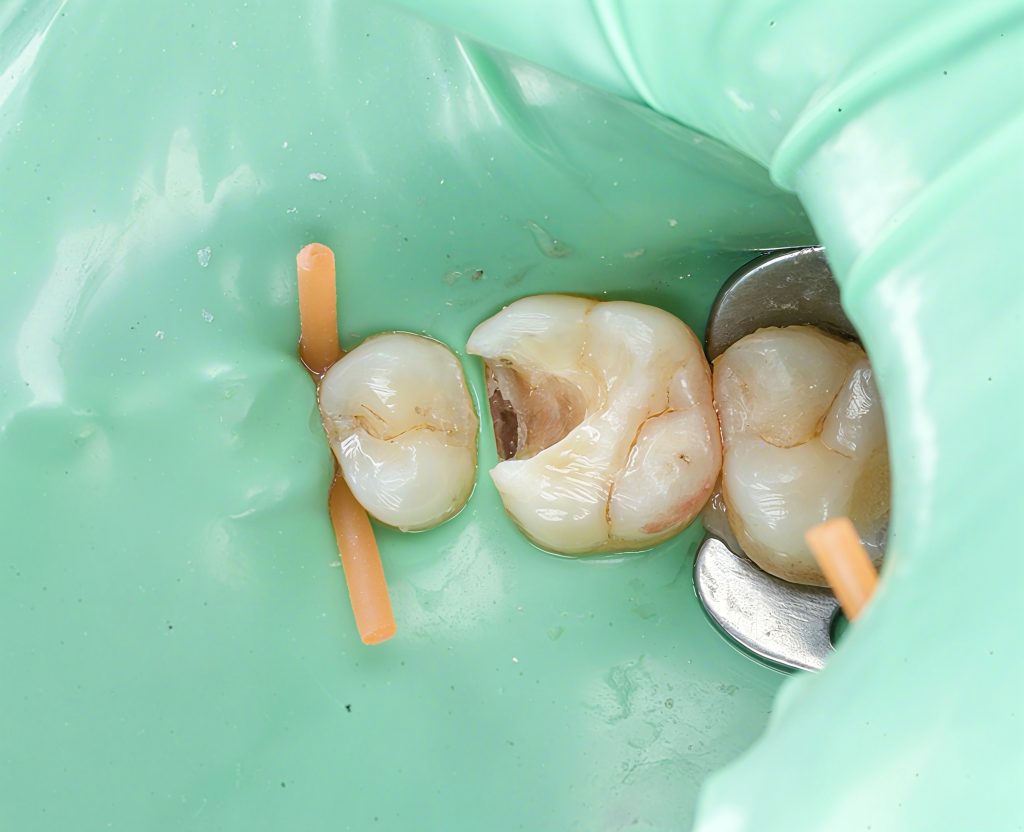

2. Isolation & Access

Rubber dam placement ensured a clean field.

Only undermined enamel and infected dentin were removed—nothing more.